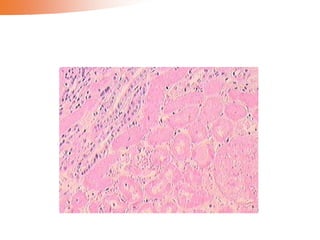

Microscopically, the nutmeg pattern results from congestion around

the central veins, as seen here. This is usually due to a "right sided" heart failure.

• Microscopic changes in ‘nutmeg’ liver:

1) Atrophy and/or necrosis of the liver cells in the

mainly in centrilobular regions

2) Fatty change of the liver cells in the peripheral

part of the lobules

28 Microscopically, the nutmegpattern results from congestion around the central veins, as seen here. This is usually due to a "right sided" heart failure.

• Microscopic changesin ‘nutmeg’ liver: 1) Atrophy and/or necrosis of the liver cells in the mainly in centrilobular regions 2) Fatty change of the liver cells in the peripheral part of the lobules